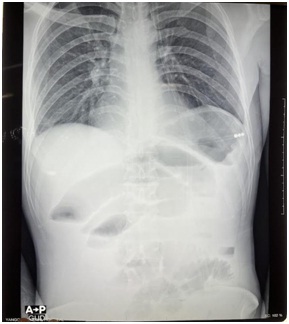

Plain-X-ray of the abdomen showed dilated small bowels. (Figure 1)

Fig1– Plain-X-Ray of abdomen (erect) showing dilated small bowels